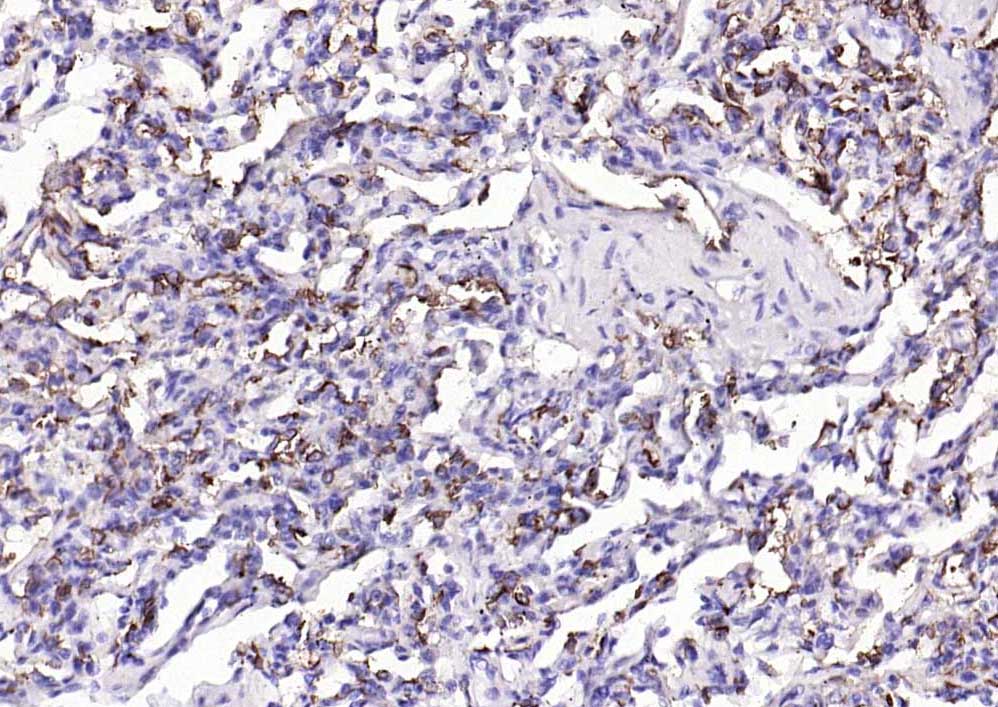

IHC-PHuman1:100-500

交叉反应: Human